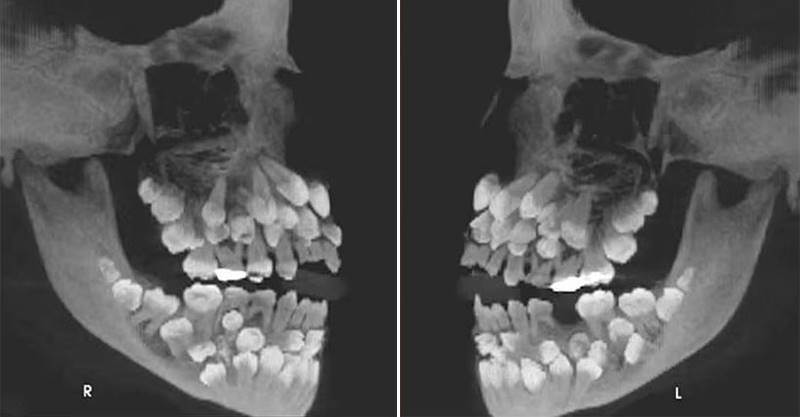

一名11歲的巴西女童因乳牙搖搖欲墜,到牙科診所看診,怎料醫生在拍完X光後,發現她嘴裡竟塞了81顆牙齒!

根據媒體《Chosun Biz》的報導,《美國齒顎矯正與顏面矯形學期刊》2011年曾刊登一起罕見病例,巴西一名11歲女童因想拔除一顆上排乳牙就醫,起初牙醫進行口腔檢查時並無異狀,誰知在照完X光後醫生大驚失色,因為女童嘴裡竟藏了18顆乳牙、32顆恆牙,以及31顆多生牙,一張小嘴共擁有多達81顆牙齒。